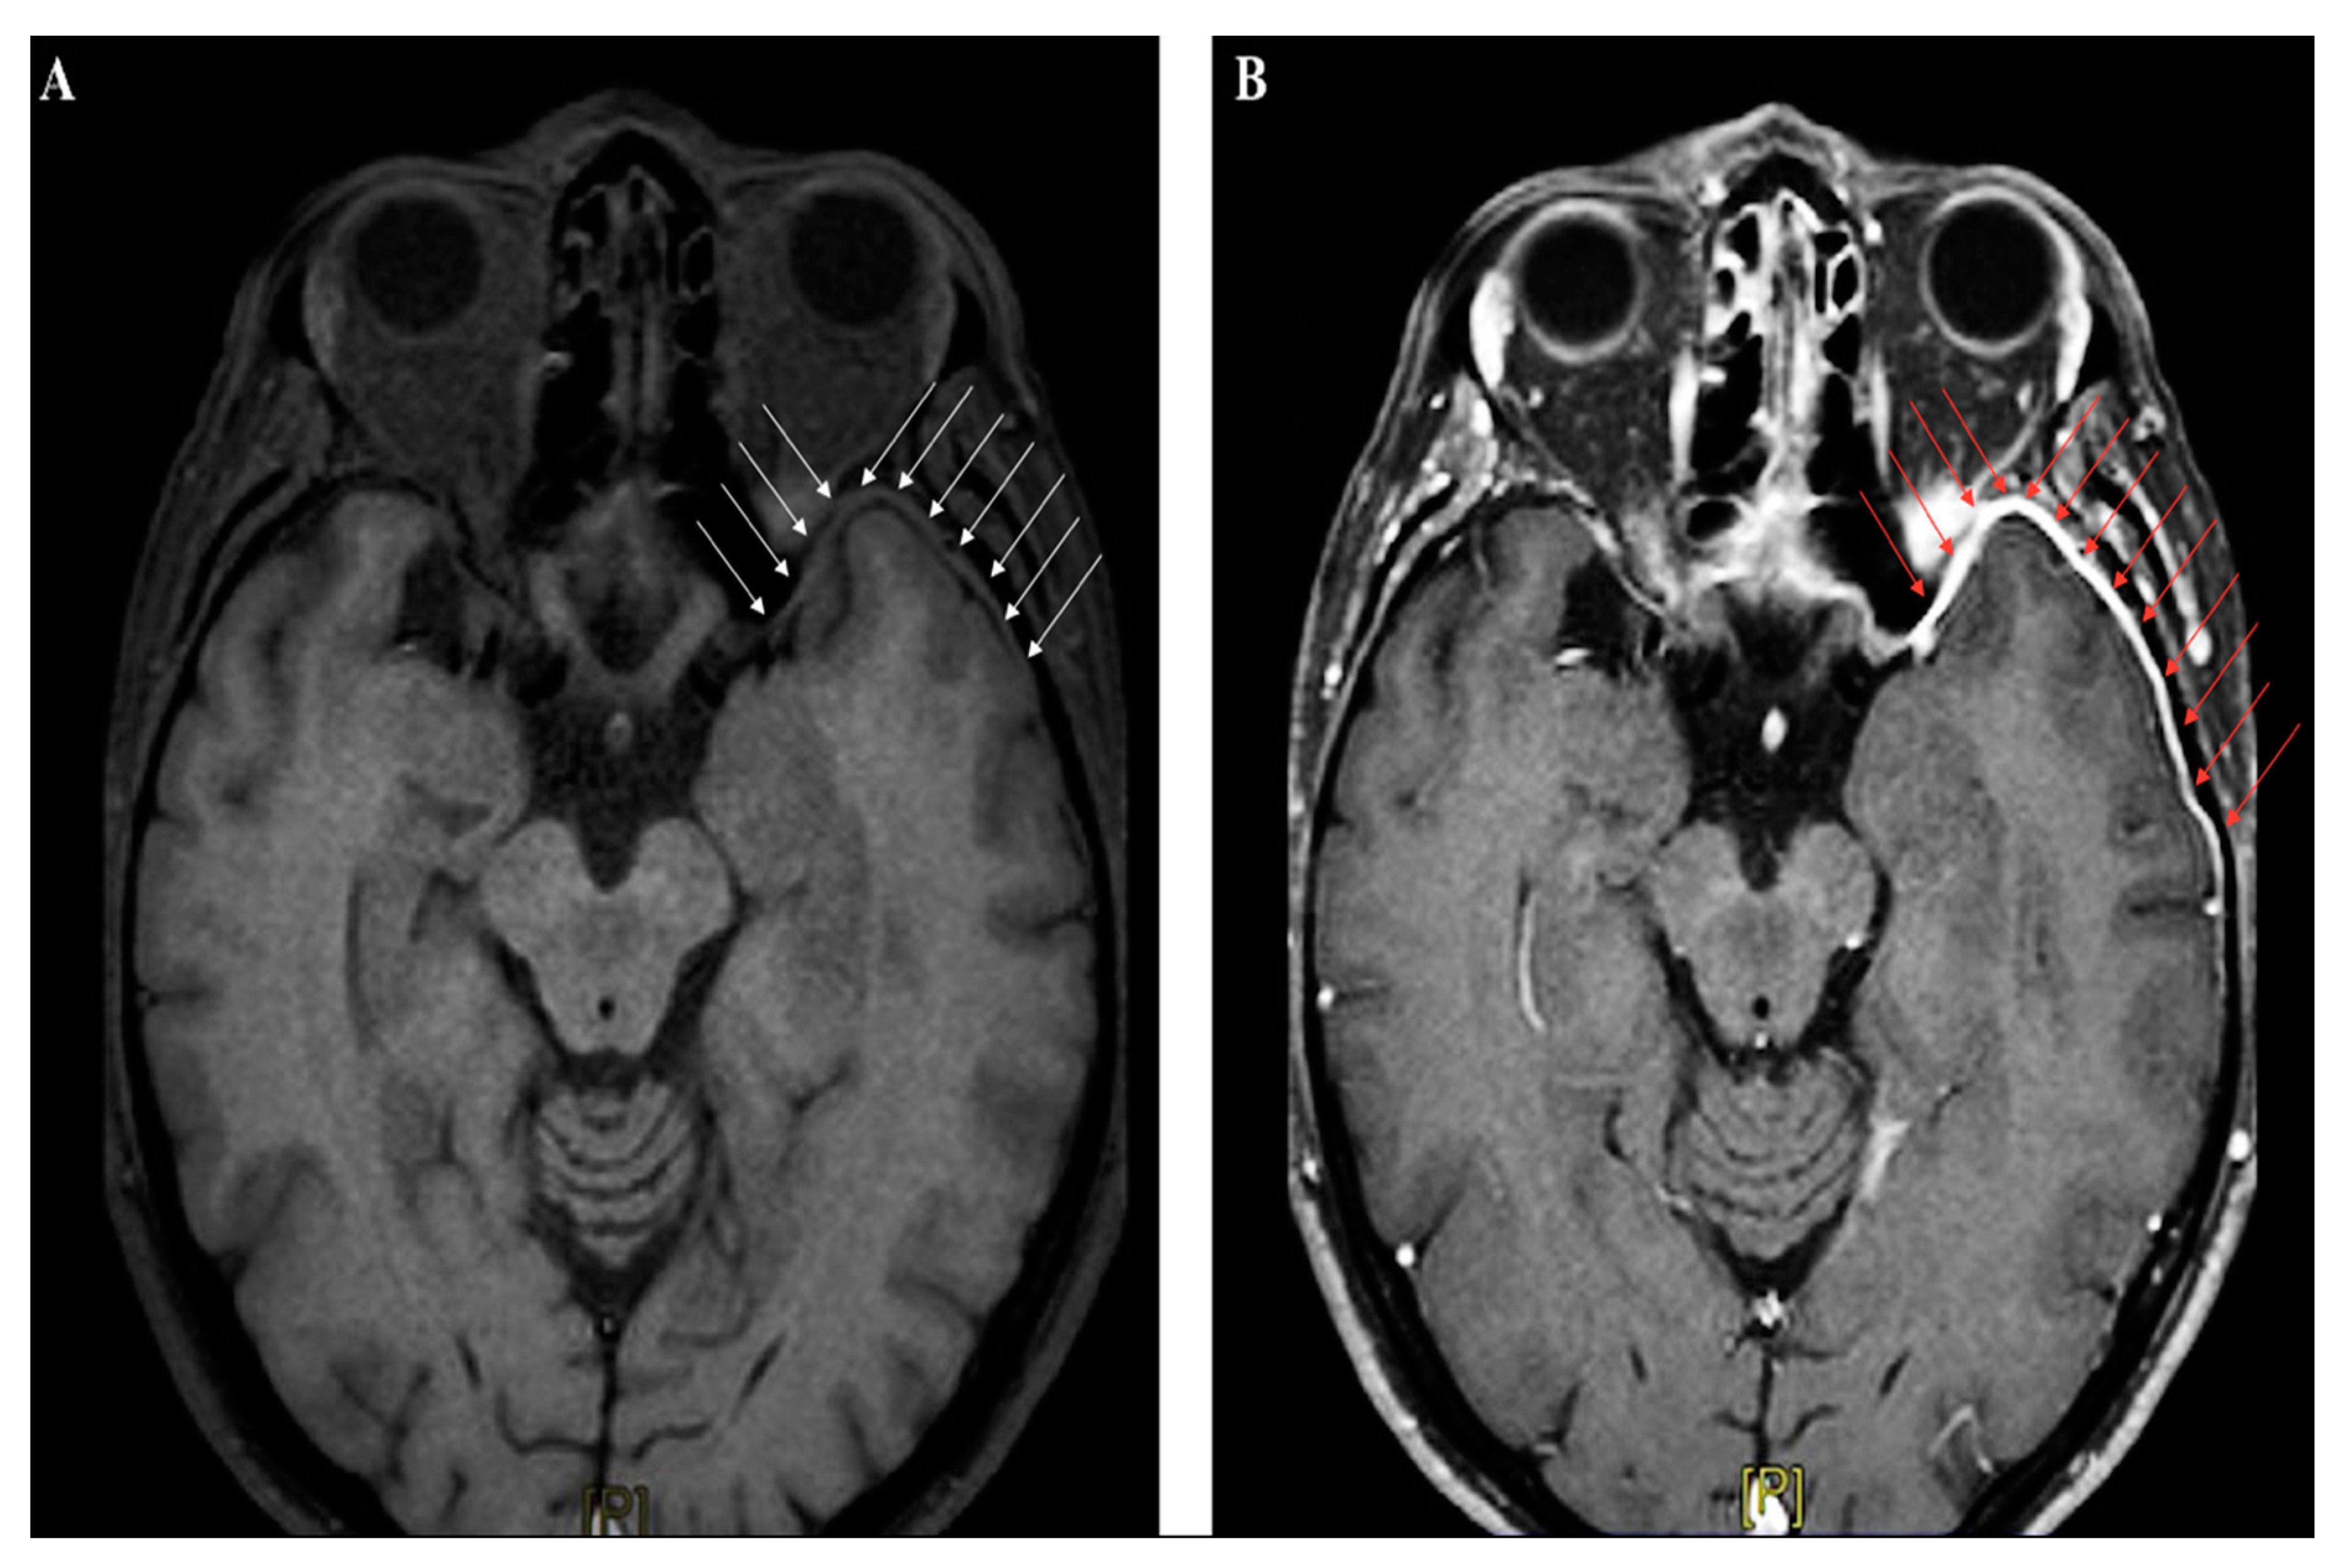

4.4.3. The Role of Neuroimaging in Meningitis

Neuroimaging studies are not crucial for meningitis diagnosis, apart from their role in identifying patients at risk for brain herniation, who should not undergo lumbar puncture. In the early phase, abnormal findings are seldom detected by CT scan; in the Dutch cohort study on community-acquired meningitis, CT was performed on admission in 71% of subjects, and was unremarkable in almost 66% of them [17]. Contrast-CT might identify meningeal enhancement in a minor proportion of cases later on in the disease course. Magnetic resonance imaging (MRI) is not immediately required in uncomplicated meningitides, although gadolinium-enhanced MRI (Gd-MRI) can clearly document the meningeal involvement (Figure 3A–B).

Figure 3.

Brain magnetic resonance imaging (MRI) (axial section, T1-weighted images) performed in a patient with recurrent headache and diplopia, and a history of remote head trauma; a definite thickening of the meningeal lining over the left anterior temporal lobe (white arrow panel A), with following contrast enhancement (red arrow panel B), can be clearly identified.

However, Gd-MRI is crucial for detection of harmful complications such as cerebral ischemia, sinus thrombosis, brain abscess, hydrocephalus, and cerebral edema. Therefore, it should be promptly performed in patients with new-onset focal neurological deficits and seizures, or other signs of clinical deterioration [38,39]. In subjects presenting with TBI, neuroimaging studies are mandatory to detect skull fractures, intracranial bleeding, cerebral edema, and diffuse axonal injury. Brain imaging also play a pivotal role in localizing CSF fistulas, even when no CSF leak is clinically evident (because of meningocele, herniation, bone fragments, or blood clots temporarily obstructing the dural tear) [10]. The early identification of CSF fistulas is strategic to plan therapeutic approaches and estimate the risk of developing post-traumatic meningitis. With this aim, several advanced techniques have been applied, such as high-resolution CT (HRCT), which uses 1–2 mm sections in both the coronal and axial planes to obtain detailed images of the bone structures, or MRI cisternography, a non-invasive technique where T2-weighted images with fat suppression and image reversal allow to highlight CSF and brain parenchyma, despite poor bone definition [10]. However, the current radiological gold standard for identification of the exact site of CSF leak implies the intrathecal injection of a detectable dye, such as fluoresceine (used off-label) or radiopaque contrast followed by CT scanning (so-called CT cisternography), or even (less common) a radioactive substance, used in radionuclide cisternograms [11]. Despite their good sensitivity, these techniques have serious potential complications, including aseptic meningitis due to intrathecal injections of chemical compounds.